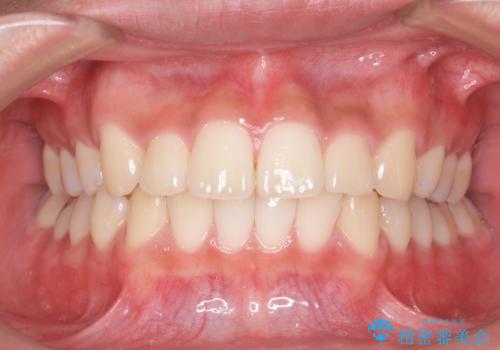

抜歯矯正の長期予後(術後8年目)

- ワイヤー矯正による治療後7年以上経過した患者様です。当時上の小臼歯を2本抜歯しています。

10代で矯正治療を行い、現在20代になられています。

矯正後8年目になりますが、並びも綺麗に保持でき、また上下の歯がさらにしっかり咬んできているのがわかります。

定期的にメンテナンスにきていただき、特に歯の健康状態にも問題がありません。